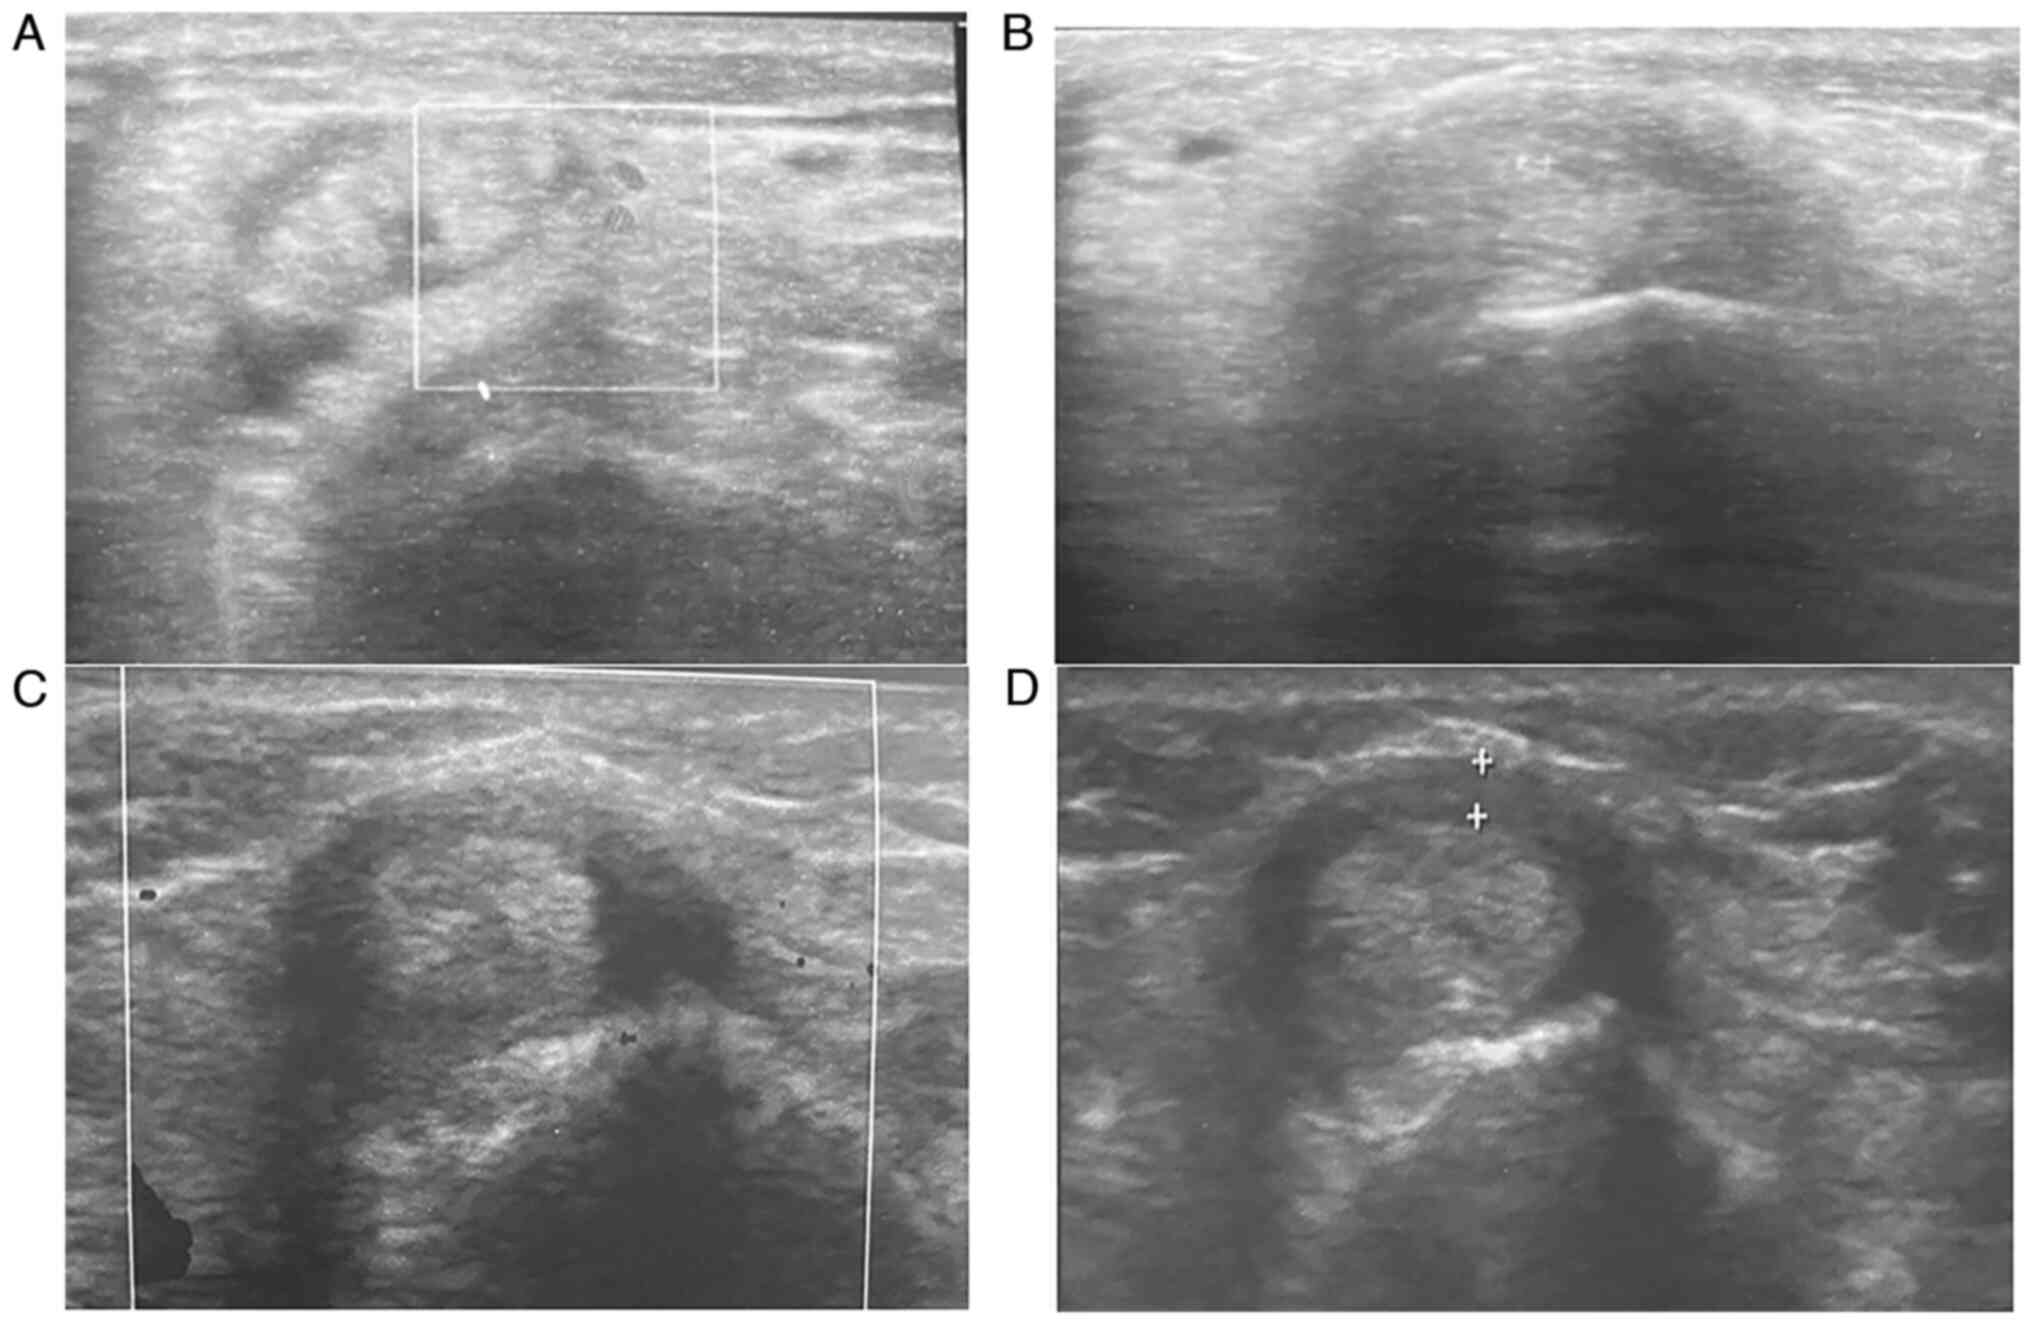

Baseline sonographic findings (as presented in Table III) revealed a thickened retinaculum (1.89±0.5; ranging from 1.3-3 mm) and tendon sheath effusion (2.07±0.52) in all patients (illustrated in Figs. 1 and 2). As regards anatomical variations, 5 patients (41.7%) had septum between APL and EPB, and 4 patients (33.3%) had accessory tendon slips (example illustrated in Fig. 1). However, post-PRP injection, a US examination at the 1- and 3-month follow-up periods revealed a significant improvement in the patients. The thickness of the extensor retinaculum had progressively decreased, from a mean of 1.89 mm pre-injection to a mean of 1.3 mm and 0.96 mm at the 1- and 3-month follow-up, respectively (P<0.001). The tendon sheath effusion observed in all the patients had a mean thickness of 2.07 mm pre-injection. At the 1-month follow-up, effusion was observed in 11 cases (91%) with a mean thickness of 1.6 mm, and at the 3-month follow-up, only 7 of the cases had effusion (58%) with a mean thickness of 0.73 mm (P<0.001). Peri-tendinous hyperemia was initially observed in 7 patients (58.33%), and after the PRP injection this was only observed in 2 patients (16.7%) at the 1-month follow-up (P<0.063) and in no patients (0%) (P<0.001) at the 3-month follow-up (Table III; examples illustrated in Fig. 3). Sonographic improvements observed in two different patients are illustrated in Figs. 4 and 5.

Figure 4

Ultrasound examination of the left wrist of a 60-year-old female patient. (A) Evidence of hyperemia) and (B) evidence of retinaculum thickness before treatment; (C and D) at 3 months after the platelet-rich plasma injection, indicating no evidence of (C) hyperemia and (D) a prominent decrease in retinaculum thickness.

Figure 5

Ultrasound of the first dorsal compartment. (A) Transverse scan; (B) longitudinal scan, illustrating a thickened retinaculum; (C) peri-tendinous hyperemia in a 30-year-old female patient; (D) a prominent decrease in retinaculum thickness observed at 1 month after the platelet-rich plasma injection, which was maintained at the 3-month follow-up scan.